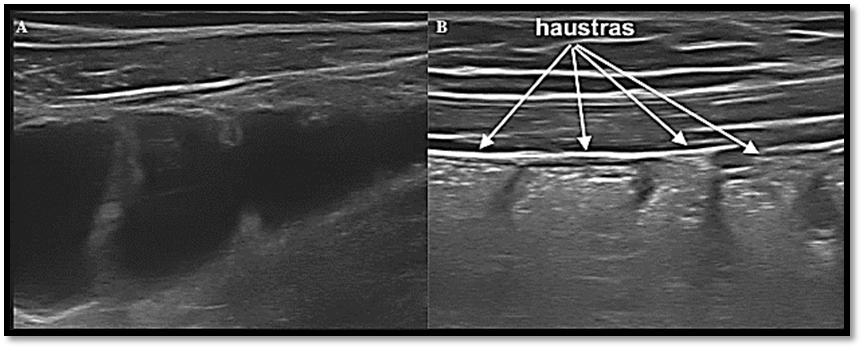

El intestino delgado se diferencia del colon por la capacidad peristáltica continua, trayecto sinuoso y por la presencia de las válvulas conniventes, las cuales son más expresivas al existir contenido líquido y en segmentos más proximales (yeyuno). Al igual que en otras técnicas de imagen, no se puede diferenciar entre asas de yeyuno e íleon. En ecografía se maneja un criterio topográfico para su identificación, de tal forma que generalmente las asas de delgado localizadas en la región infraumbilical se consideran asas de íleon y las que se localizan en región supraumbilical se consideran asas de yeyuno. El aspecto ecográfico típico del colon es la haustración y se diferencia del intestino delgado por la disposición de ondas de gas y la ausencia de peristalsis. ( IMAGEN 2 A-B).

Figura 2: B: Ecoestructura de la pared intestinal del colon en un paciente sano. (3)